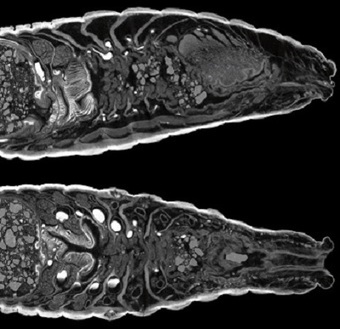

Una parte importante del conocimiento adquirido en zoología se ha logrado diseccionando animales para observar sus órganos y deducir el funcionamiento de sus estructuras.

Para no tener que andar con el animalito al colegio y matarlo para diseccioinarlo, como hacíamos antes….